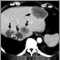

Pancreatic cancer, CT scan